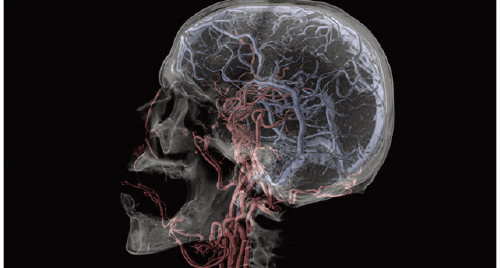

Based on the previously stored information, the areas recognized as blood vessels are extracted.

Vessels are extracted with one click by using image recognition technology.

Cerebral Arteries and Vein separation